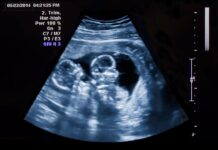

Сильное или многократное обвитие пуповиной несет риск нарушения кровоснабжения плода и развития внутриутробной гипоксии. Не менее серьезную угрозу представляет и тугой узел: он сжимает сосуды, что может привести к дефициту кислорода у ребенка и повышает вероятность опасных ситуаций в родах. К сожалению, выявить патологию до родов проблематично: ультразвуковое исследование фиксирует узлы лишь в 12% случаев, чаще всего их обнаруживают неожиданно уже в родильном зале.

В этот раз процесс родоразрешения проходил сложнее. Медики диагностировали у малыша повторяющиеся эпизоды брадикардии (снижение частоты сердечных сокращений), связанные с передавливанием пуповины. Для бережного и скорейшего завершения родов использовали метод вакуум-экстракции. После того как появилась головка малыша, на его шее обнаружилось плотное однократное обвитие, которое аккуратно сняли. В ходе дальнейшего обследования пупочного канатика выявили еще два истинных узла, однако без критического сжатия.